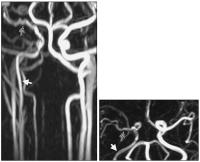

Abbildung 1: MR-Angiographie (3D-PCA): Die perfundierten Gefäßlumina sind geschwindigkeitskodiert dargestellt. Die Arteria carotis dextra (weißer Pfeil) zeigt eine im Seitenvergleich moderate Flußverlangsamung im verschmälerten perfundierten Lumen. Auch die Arteria cerebri media dextra weist diesbezüglich deutliche, vergleichbare Veränderungen auf (schraffierter Pfeil).